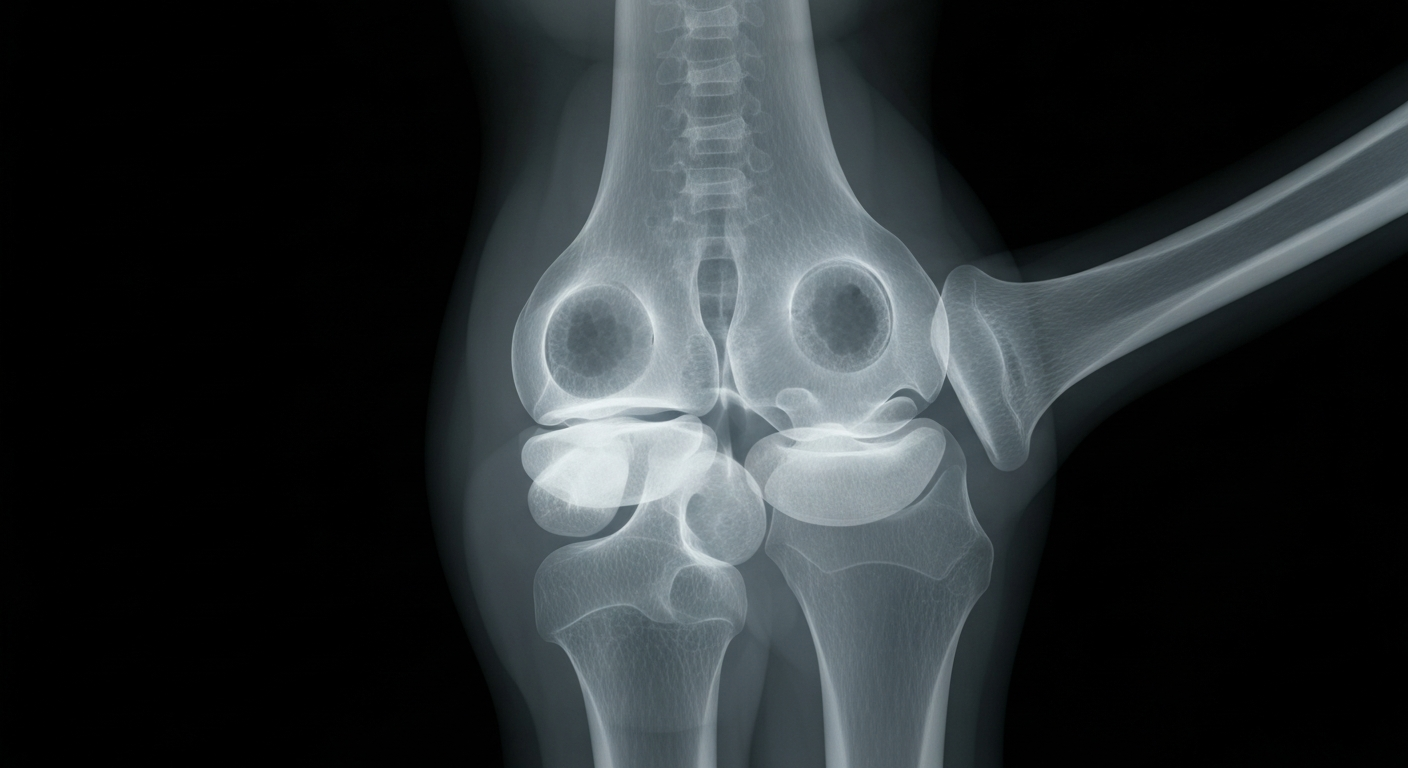

An X-ray view of an inflamed joint, highlighting the potential of PEPITEM to reduce swelling and prevent further damage in inflammatory arthritis.Birmingham TodayPEPITEM, a naturally occurring immunopeptide, has demonstrated promising results in both human and animal studies for reducing inflammation and joint damage associated with rheumatoid arthritis (RA) and psoriatic arthritis (PsA). Scientists at the University of Birmingham, who discovered PEPITEM, found it could prevent the onset of disease and significantly reduce joint swelling in animal models, with results comparable to current standard treatments.